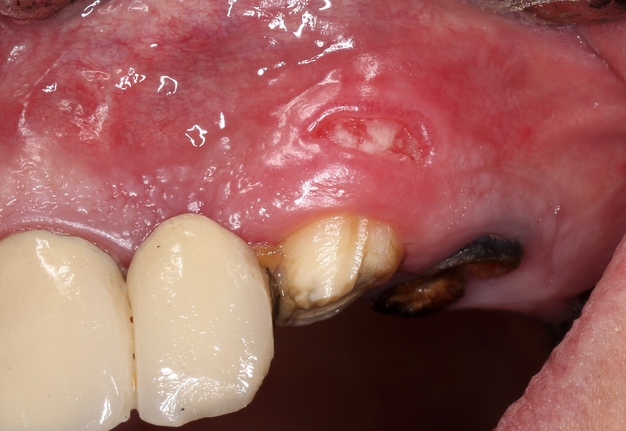

One of the postulates of “The golden rules of the flap design” reads, “The incision must never cross a bone defect. Incisions should be made away from the lesion if possible” [29]. More recent research also supports this view “The underlying apical lesion or surgical bony access must not extend to the flap margins” [16]. Using CBCT, the surgeon can accurately measure the size of the bone defect and plan the incision design so that the incision is at a distance from the bone defect (or the area where the osteotomy will be performed). If the surgery is not planned carefully and the incision passes through a bone defect, the risk of complications associated with healing increases significantly. There is the risk of postoperative infection [12]. These complications are sometimes observed (Fig 6).

One of the less well-described, rare and late complications of the Ochsenbein-Luebke incision is the occurrence of fenestrations in the soft tissues with baring bone. These fenestrations can be located both in the area of ​​the attached gingiva, which corresponds to the horizontal component of the incision (Fig 15), and on the transition of attached gingiva into the alveolar mucosa, which corresponds to the vertical component of the incision (Fig 16).

The development of soft tissue fenestrations with associated bone exposure is predominantly linked to a thin gingival biotype, suboptimal flap design, and inadequate wound closure.